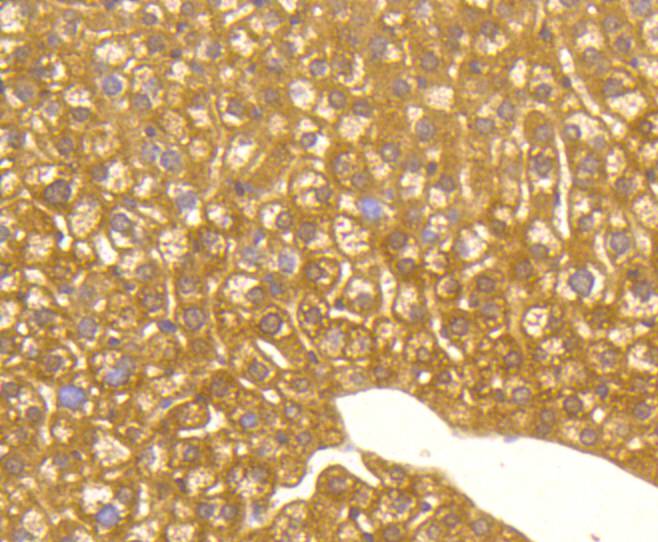

Immunohistochemical analysis of paraffin-embedded mouse liver tissue using anti-MAP1LC3A antibody. Counter stained with hematoxylin.